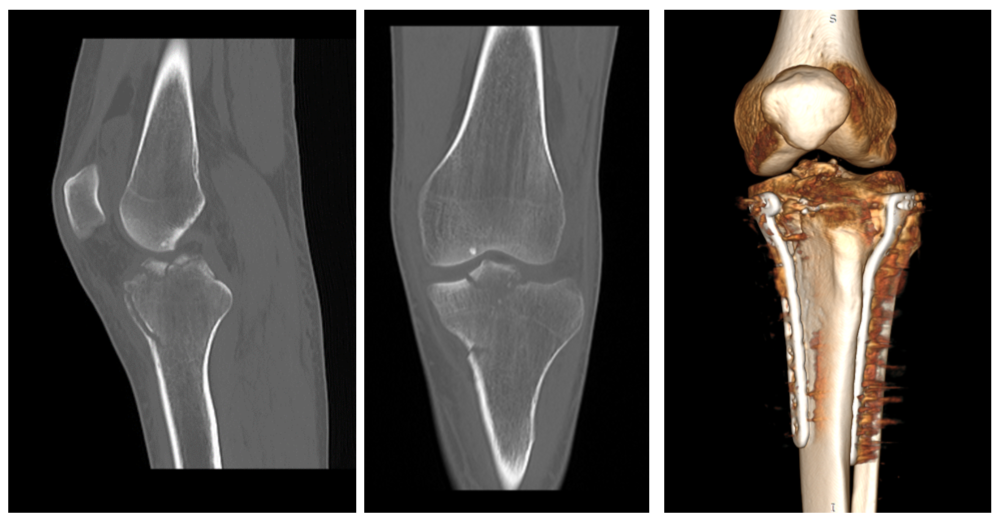

Молодой человек катается второй год, но травм раньше не получал. Он сделал обследования по рекомендации местных травматологов и в итоге решил обратиться на консультацию к специалисту Новосибирского НИИТО им. Я.Л. Цивьяна Минздрава России. По результатам дообследований был выявлен перелом проксимального отдела большеберцовой кости левой ноги с повреждением связочного аппарата, рекомендовано хирургическое лечение.

«Проведение хирургического вмешательства заняло около 3 часов. Операция проводилась под артроскопическим контролем. Мы выполнили репозицию перелома и в положении репозиции зафиксировали костные отломки специальными пластинами и винтами. Затем — рефиксация передней крестообразной связки: поскольку связка оторвалась вместе с костным фрагментом, необходимо было её повторно зафиксировать.

Для восстановления функциональности ноги пациенту нужно соблюдать ортопедический режим, носить тутор в течение 3 недель и передвигаться при помощи костылей до 2 месяцев», — комментирует заведующий травматолого-ортопедическим отделением №4 Александр Алекперов, проводивший операцию.